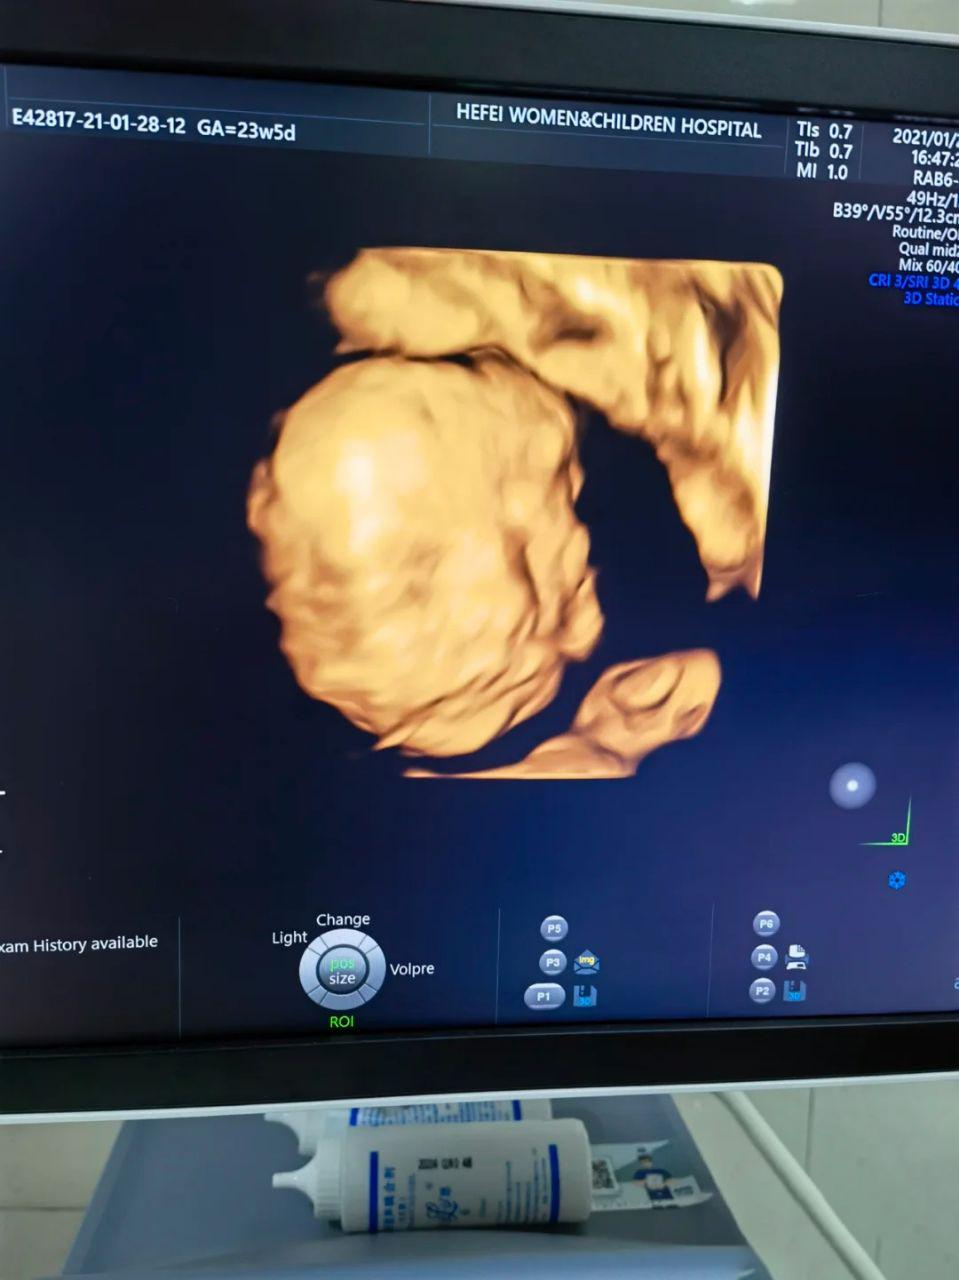

第一天四维是孕23周+3天,在公立医院做的,约的是下午,宝宝非常不配合,导致一下午做了三次勉强算是通过了。

第一次趴着贴在肚皮上,脸和脊柱都照不到,医生尽可能采集数据后,我就去走路了♀️

你二次是半个小时后,确实是转了,但是是平转,没有翻过来,所以还是看不见,继续去走路,还吃了几颗巧克力(还没做糖耐,巧克力吃的我心惊胆颤)第三次又过了半小时,我出去找罗森吃了碗关东煮,喝了两杯阿华田,感觉他动了两次,赶紧回去找医生,勉强翻过来了,数据什么的能采集到,排畸能过去就行,于是就结束了四维的检查.